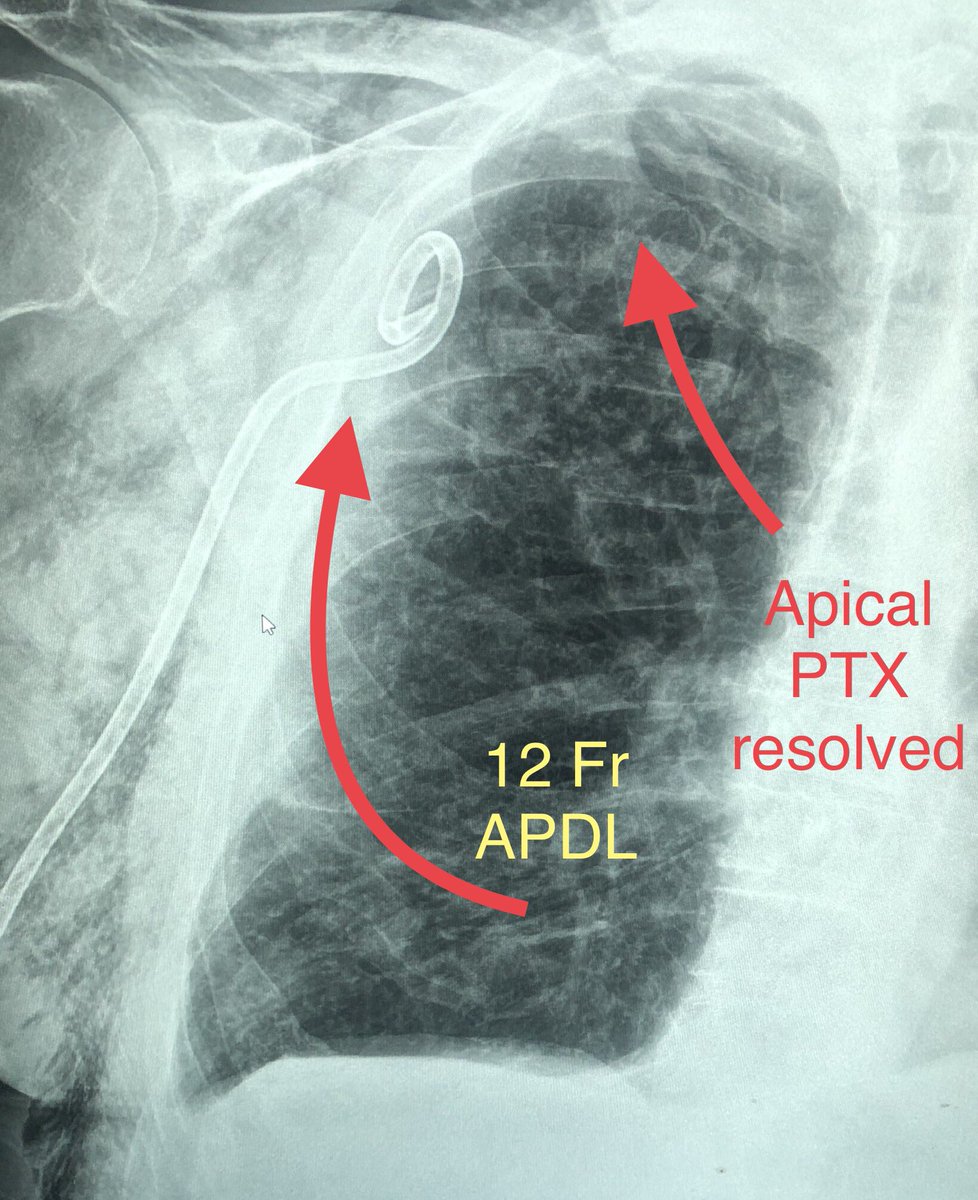

@masi_zachary @SIR_ECS @bachakzaimd @sarelgaurmd @joeirad Classic fissural chest tube. Love these cases. Fluoro guidance? How do you like APDL vs dawson mueller for your PTX chest tubes? And how do you decide your sizing? I usually do anterior approach 8.5 Fr dawson mueller